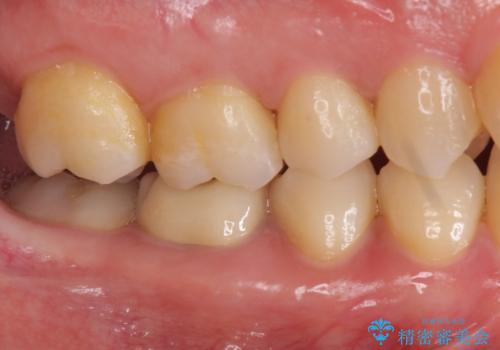

- 右下の奥歯に入れた銀歯を白くしたいとのことで来院されました。

根っこの治療がされていますが、症状もなくレントゲン画像で病変も確認できないため根管内には触れず被せ物のやり替えのみとなりました。

下の奥歯は口を開くと簡単に外から見えてしまいます。

銀色だった歯が白くなったことで大変喜んでいただけました。